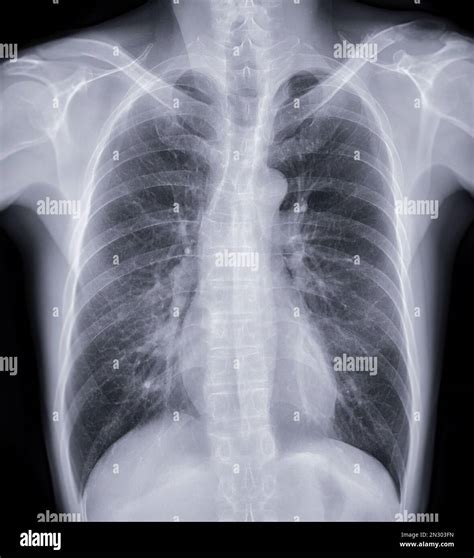

Interpreting Tb X Ray Results

Interpreting Tb X Ray results requires expertise and experience. Radiologists look for specific signs that may indicate TB:

• Cavities: These are hollow spaces in the lungs that can form as the body tries to contain the infection.

• Nodules: Small, round opacities that can be indicative of TB infection.

• Infiltrates: Areas of increased density in the lung tissue, often seen in active TB.

• Pleural Effusion: Fluid accumulation in the pleural space, which can be a complication of TB.

It’s important to note that while Tb X Ray can provide valuable information, it is not always conclusive. Additional tests, such as sputum tests or CT scans, may be required for a definitive diagnosis.